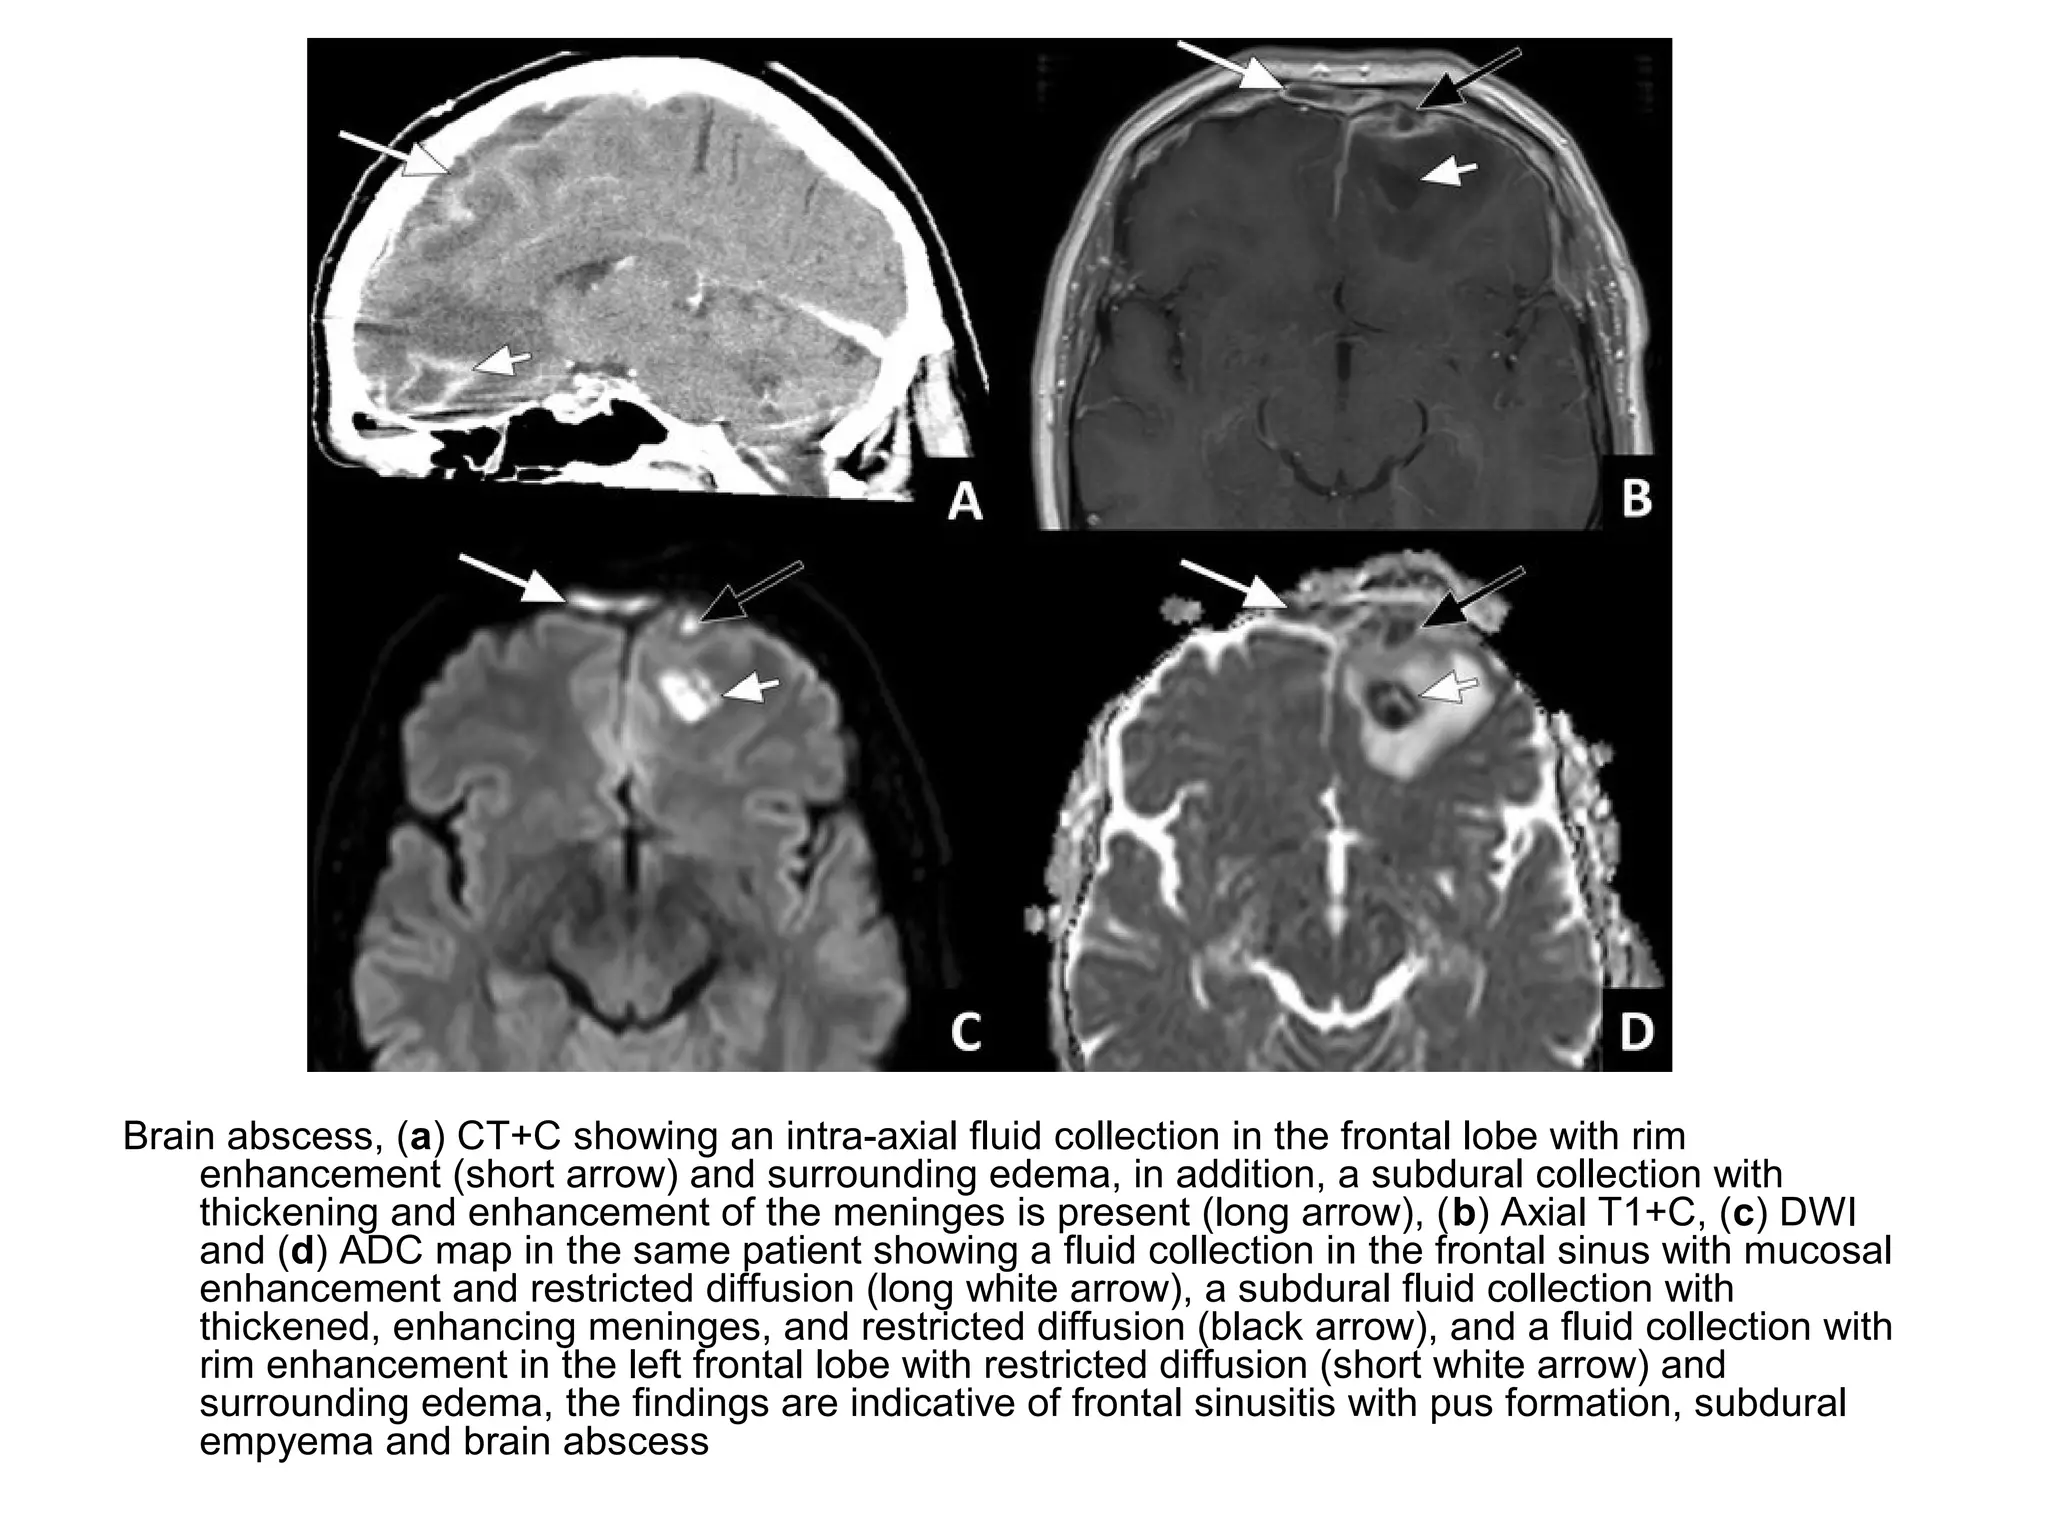

Brain abscess, (a) CT+C showing an intra-axial fluid collection in the frontal lobe with rim

enhancement (short arrow) and surrounding edema, in addition, a subdural collection with

thickening and enhancement of the meninges is present (long arrow), (b) Axial T1+C, (c) DWI

and (d) ADC map in the same patient showing a fluid collection in the frontal sinus with mucosal

enhancement and restricted diffusion (long white arrow), a subdural fluid collection with

thickened, enhancing meninges, and restricted diffusion (black arrow), and a fluid collection with

rim enhancement in the left frontal lobe with restricted diffusion (short white arrow) and

surrounding edema, the findings are indicative of frontal sinusitis with pus formation, subdural

empyema and brain abscess